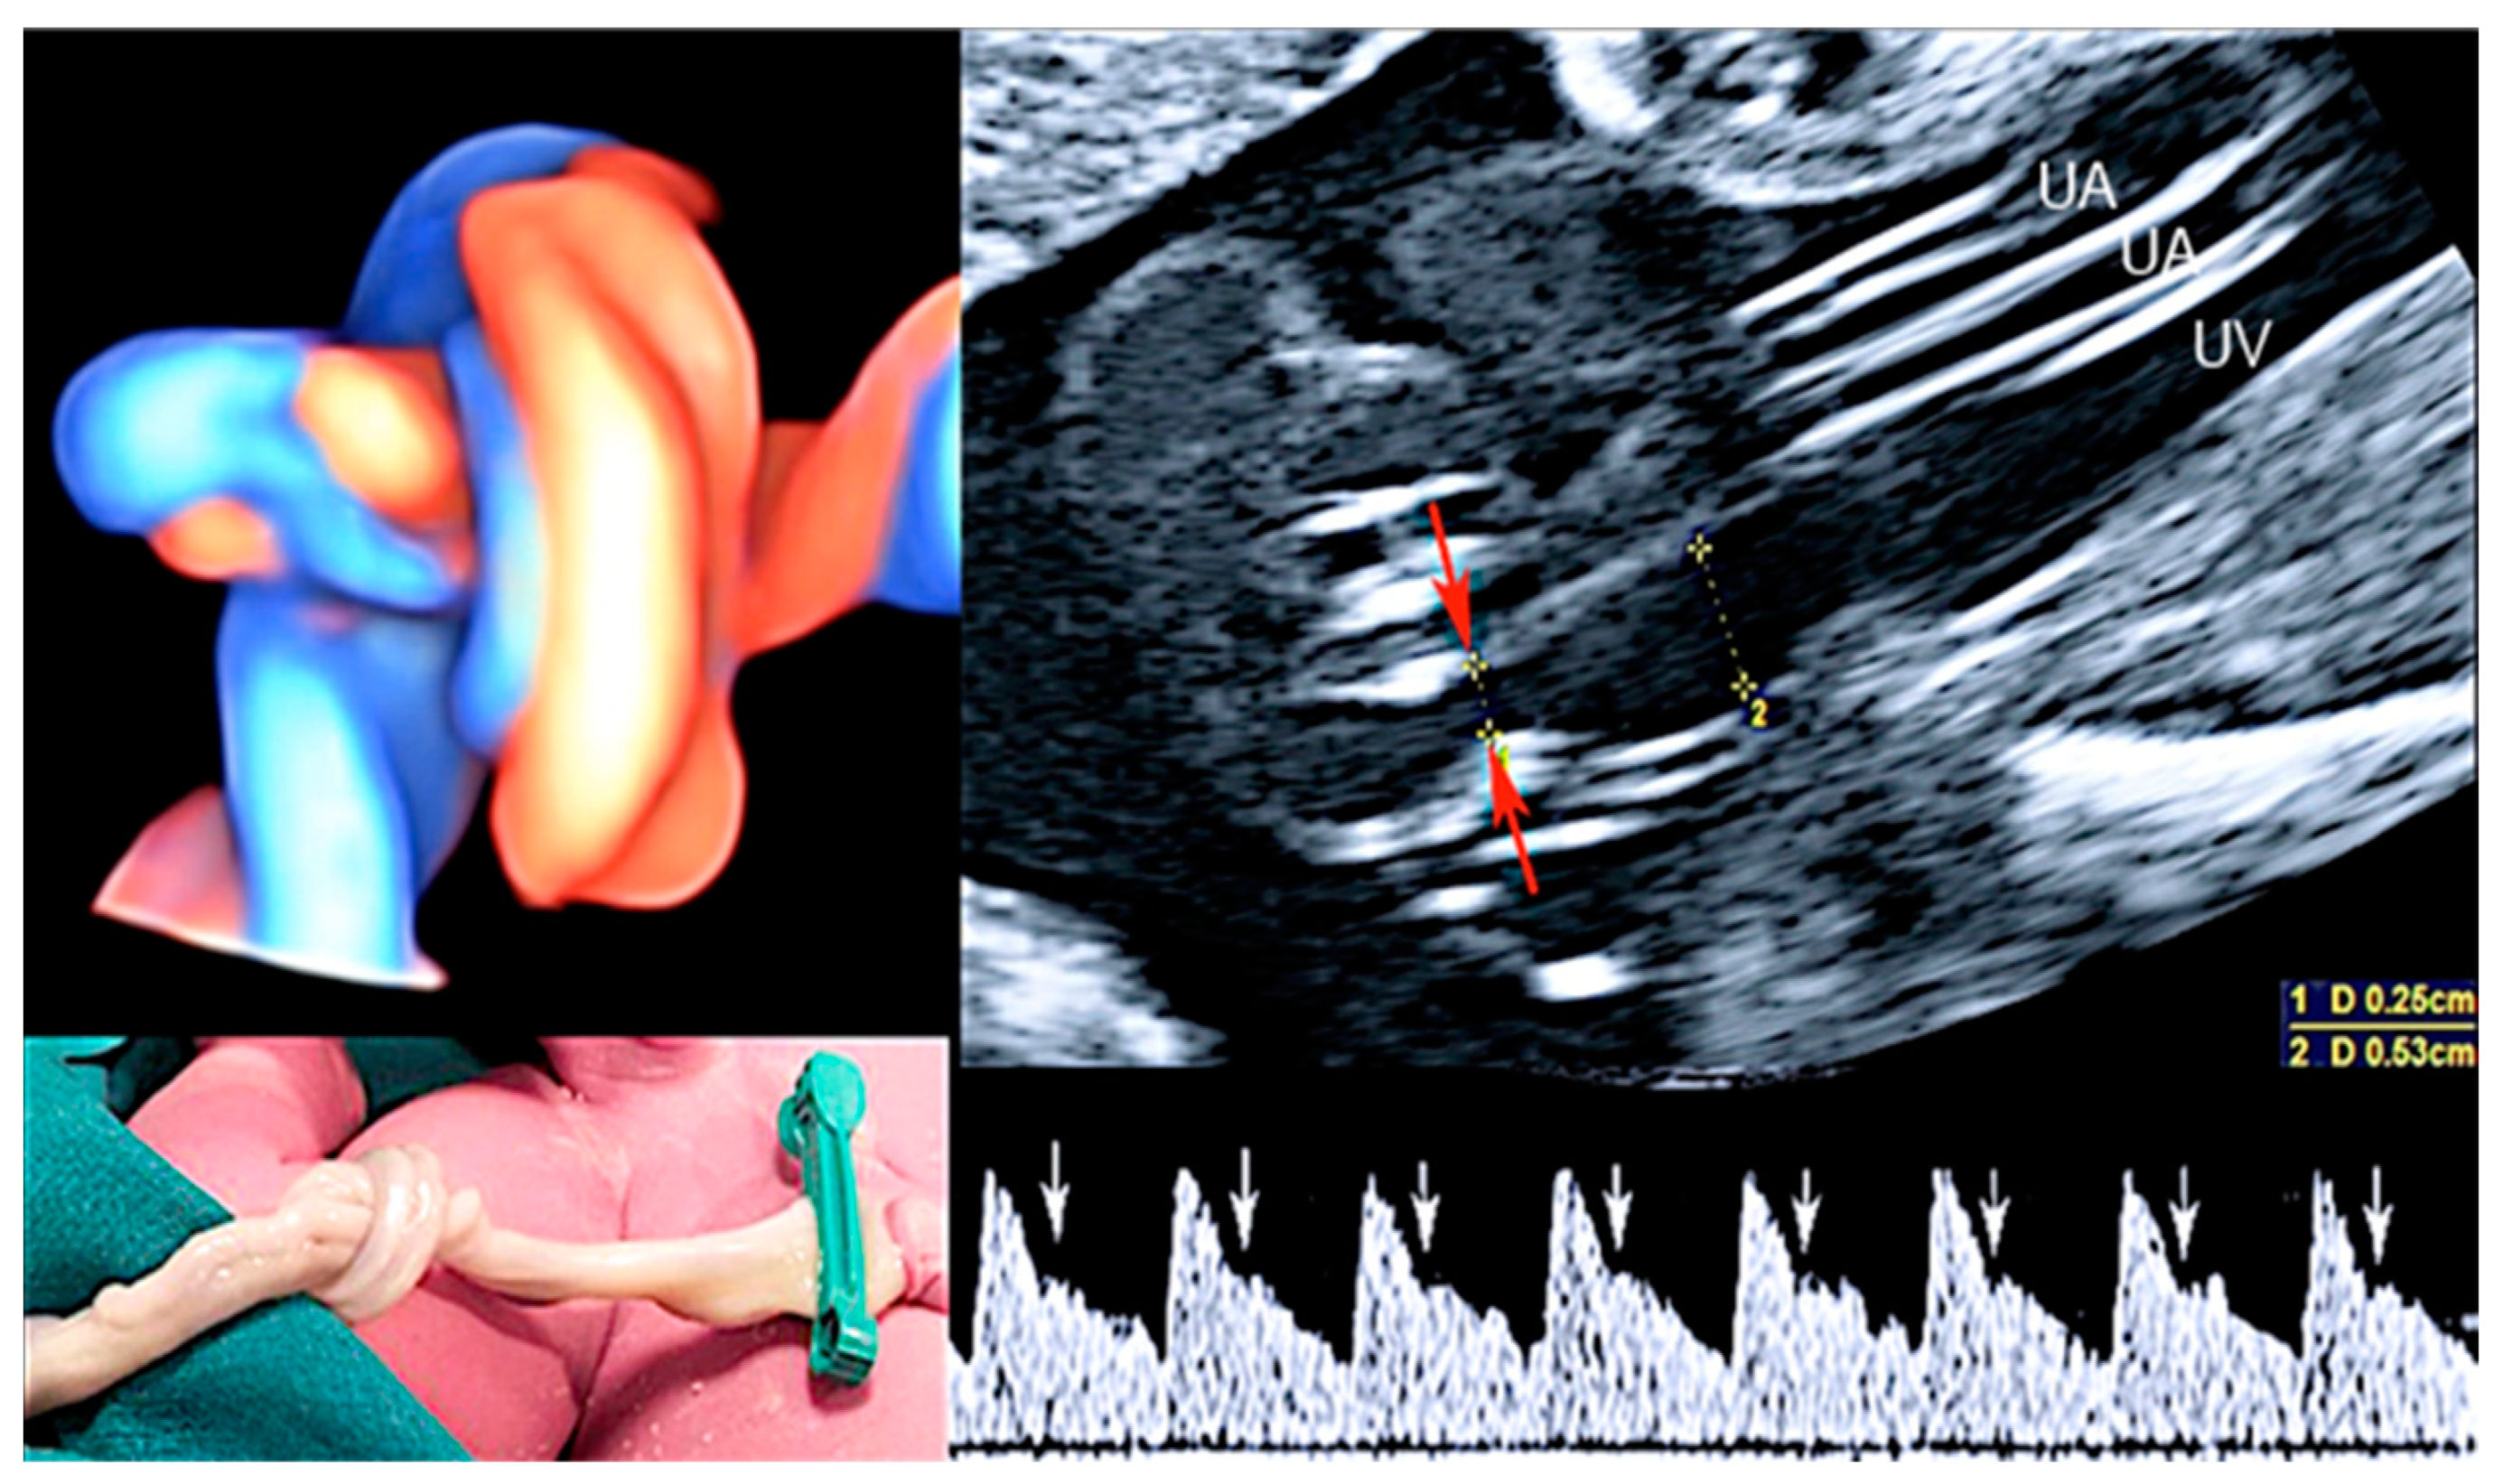

3.4. Single Umbilical Artery